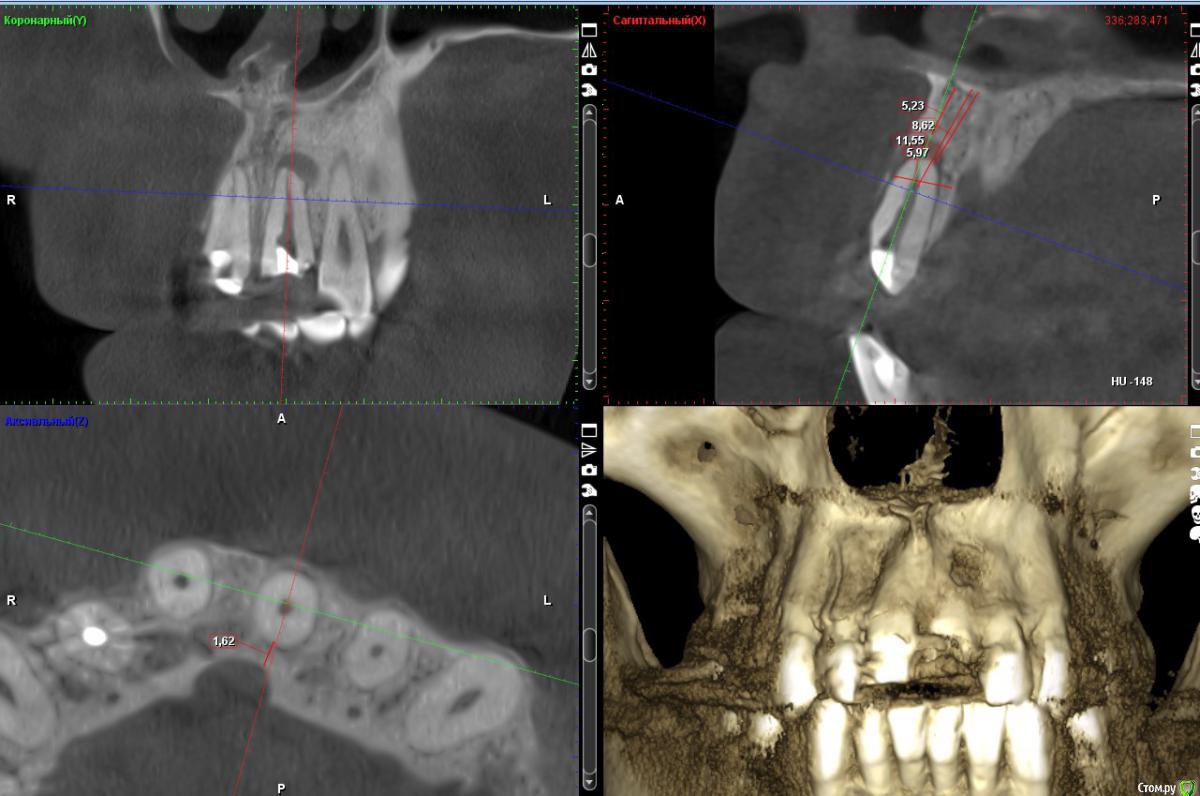

darkdiablo40 Опубликовано 8 августа, 2020 Поделиться Опубликовано 8 августа, 2020 (изменено) Здравствуйте! Поступил пациент на одномоментную имплантацию и удаление 2.1. Хотел бы обсудить с Вами случай. Что смущает: 1) Гранулема с резорбцией вестибулярной стенки в области верхушки. 2) Наличие выраженного широкого резцового канала, т.е. нельзя уйти небно. 3) Тонкая вестибулярная пластинка, нужно подумать, как лучше удалить, думается, что если удалять по классике, то рычагом вестибулярка уйдет.Сам склоняюсь к отсроченной имплантации.Предварительно мои мысли: 1) Выбрать ось имплантации соосно зубу, на несколько градусов более палатинально 2) Отслоиться достаточно хорошо, выполнить кюретаж гранулемы, осмотреть дефект 3) Установить имплантат, зазор заполнить графтом, образовавшееся окно закрыть резорбируемой мембраной.Что вы думаете об этом? Изменено 8 августа, 2020 пользователем darkdiablo40 Ссылка на комментарий

darkdiablo40 Опубликовано 8 августа, 2020 Поделиться Опубликовано 8 августа, 2020 (изменено) Собираюсь одномоментно, но смущают вышеперечисленные особенности, чтобы не привело к дефекту вестибулярной пластинки в области имплантата.Закрывать писал при одномоментной методике. Изменено 8 августа, 2020 пользователем darkdiablo40 Ссылка на комментарий